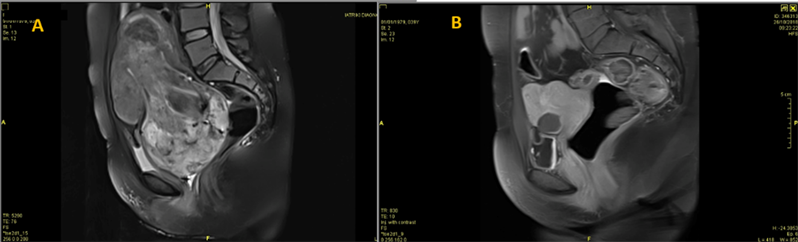

We present a 38-year-old nulliparous woman who was referred to our department for robotic fibroid enucleation. In the past, this woman had been operated three times for fibroid enucleations. She had undergone an abdominal laparotomy (9 years earlier), a laparoscopy (4 years earlier) in another institution. Finally, she had undergone a successful hysteroscopy only 7 months earlier, for a submucous fibroid which was removed resectoscopically, followed by insertion of a progesterone-releasing (intrauterine device) IUD, to facilitate endometrial healing. Recently she experienced again intense and irregular bleeding (metrorrhagia) for which she performed ultrasonography and subsequently a magnetic resonance imaging (MRI). The MRI showed several intramural fibroids, the largest of which sized 12-cm, filling the lesser pelvis (Figure 1(a)). The follow-up MRI revealed ultimate changes (Figure 1(b)).

Figure 1. (a): MRI on presentation. Sagittal plane. The fundus extends as high as L3. The lesser pelvis is filled with a large fibroid with degenerative necrosis. The cervix is not visible. (b): MRI at 6-months follow up. Sagittal plane. The pelvic anatomy is restored. Only few small intramural fibroids are seen. The endometrial cavity is distinguished.

At 6-months follow up, the patient had fully recovered and was gratified. The Hct had risen to 41 (without transfusion), menses became regular, although bleeding now lasted for only two days. Ultrasonography showed a normal functioning endometrium 7 mm in thickness. The follow-up MRI revealed ultimate changes (Figure 1(b)). The pelvic anatomy was restored.